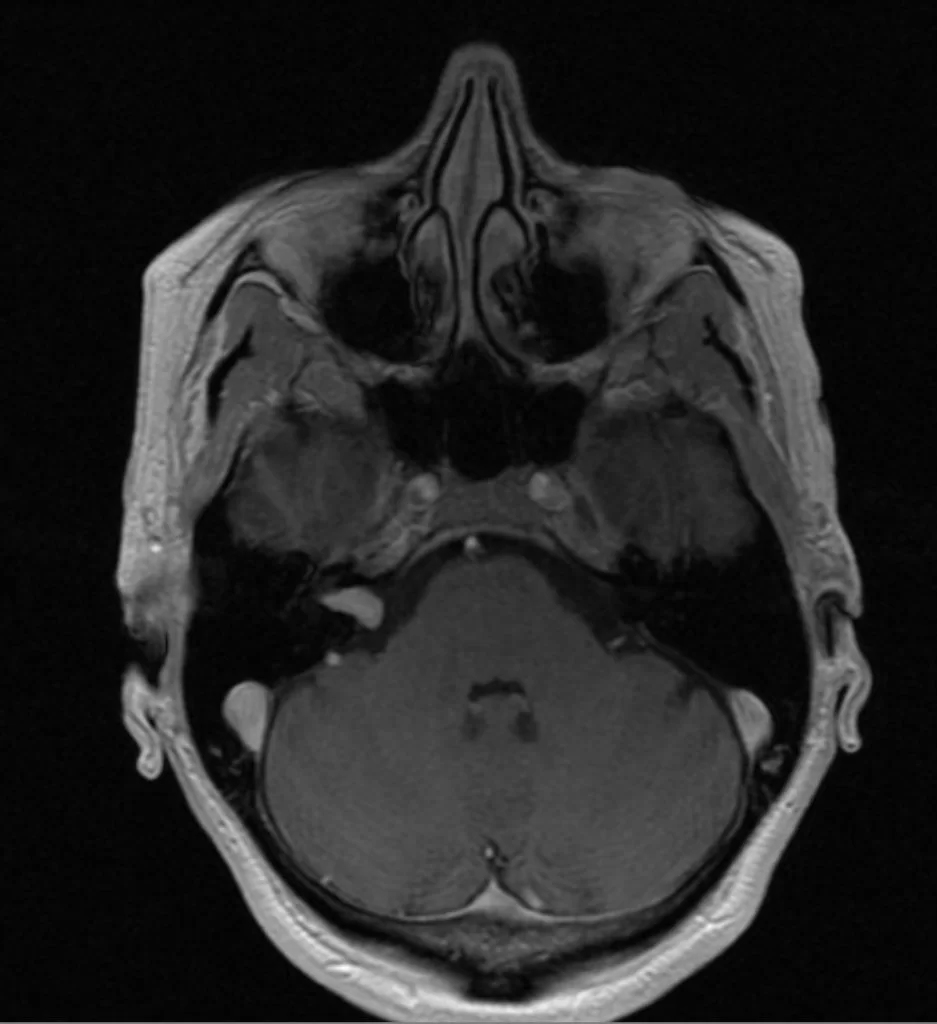

Ακουστικό Νευρίνωμα Δεξιά

Ασθενής γυναίκα 68 ετών με προοδευτική επιδείνωση της ακοής δεξιά και επεισόδια ιλίγγων και διαταραχής της ισορροπίας και βάδισης. Η